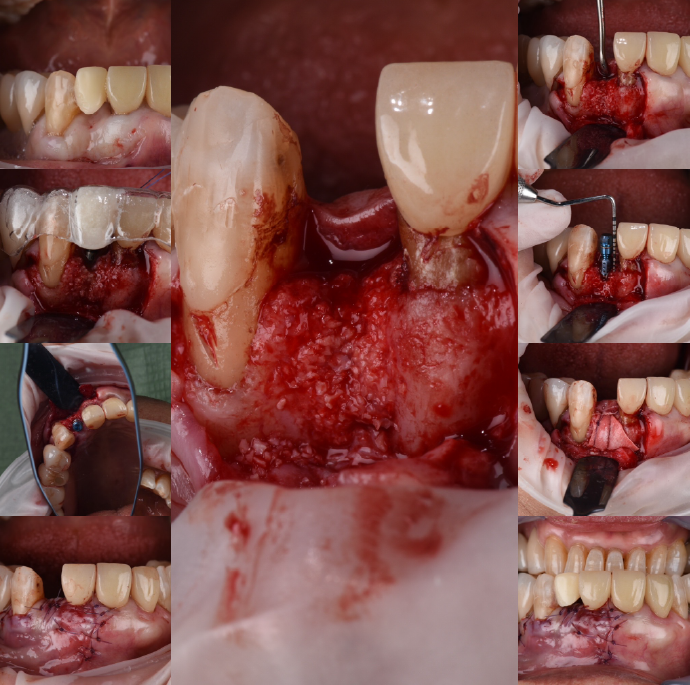

| 治療内容 | リッジプリザベーション(歯周外科)+インプラント埋入 |

| 治療費 | 総額 約60万〜 |

| 治療回数 | 10回 |

| リスク | 術部の発赤、腫脹、疼痛、部分的なネクローシス |

歯周病をしっかり改善・管理できていない場合、例えばインプラント治療を行っている方では、同じように歯槽骨に埋入された人工歯が「インプラント周囲炎」という歯周病類似の炎症に侵される可能性が高まります。

インプラントはむし歯にはなりませんが、歯周病菌に対しては脆弱で、進行スピードも速いと報告されています。

そのため、インプラント治療の前後・治療中においても、歯周病の検査・クリーニング・日々のケア・定期メンテナンスが極めて重要です。